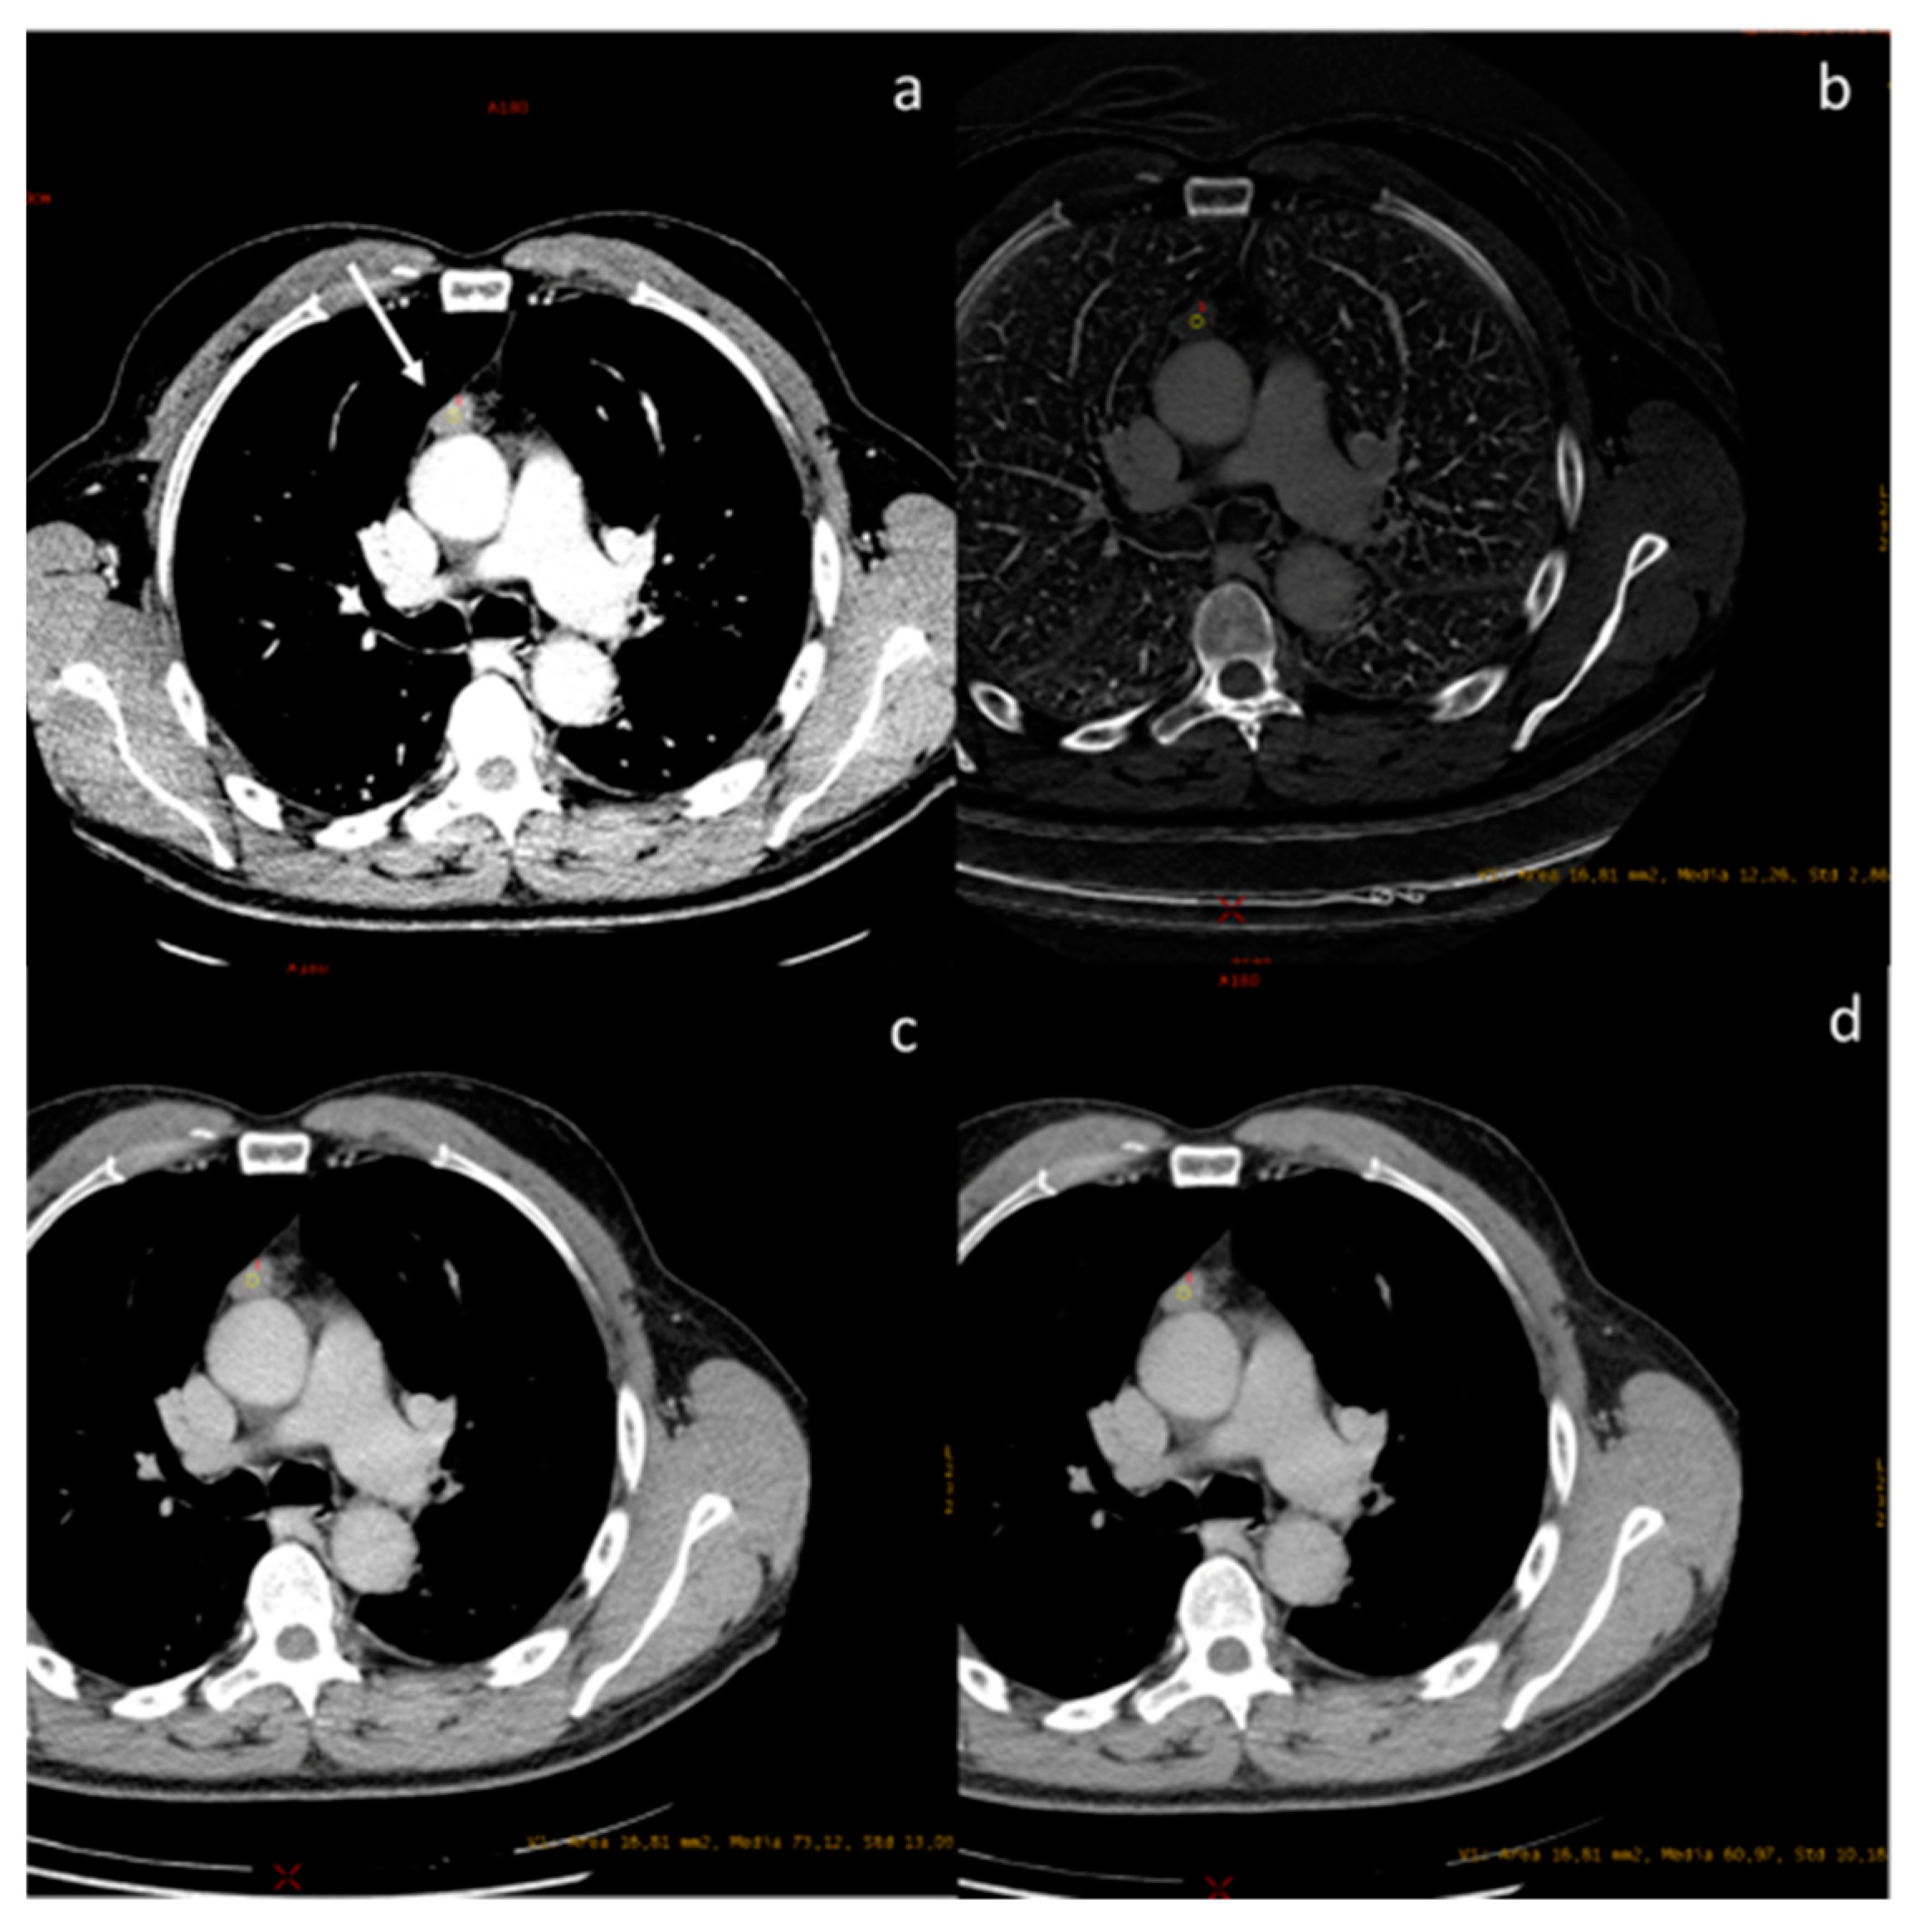

| Hagen et al. [53] Prospective study | Germany | To compare the image quality and the patient dose of contrast-enhanced oncologic chest-CT of a first-generation photon-counting CT and a second-generation dual-source dual-energy CT using comparable exam protocol settings | 100 | Somatom Definition Flash, Siemens Healthcare, Germany. NAEOTOM Alpha, Siemens Healthineers, Forchheim, Germany. Some Authors received institutional research support from Siemens | Photon-counting CT enables oncologic chest-CT with a significantly reduced dose while retaining image quality similar to a second-generation dual-source DECT. |

- Hagen, F.; Walder, L.; Fritz, J.; Gutjahr, R.; Schmidt, B.; Faby, S.; Bamberg, F.; Schoenberg, S.; Nikolaou, K.; Horger, M. Image Quality and Radiation Dose of Contrast-Enhanced Chest-CT Acquired on a Clinical Photon-Counting Detector CT vs. Second-Generation Dual-Source CT in an Oncologic Cohort: Preliminary Results. Tomography 2022, 8, 1466–1476. [Google Scholar] [CrossRef]